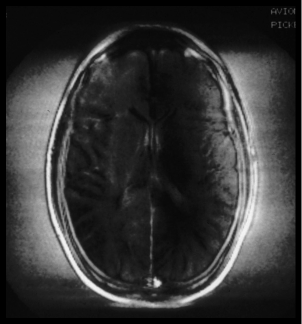

Question 57

Question

Figure 6-2 displays an example of what type of artifact

Answer

• Magnetic susceptibility

• Phase wrap

• RF zipper

• Magnetic susceptibility & RF zipper